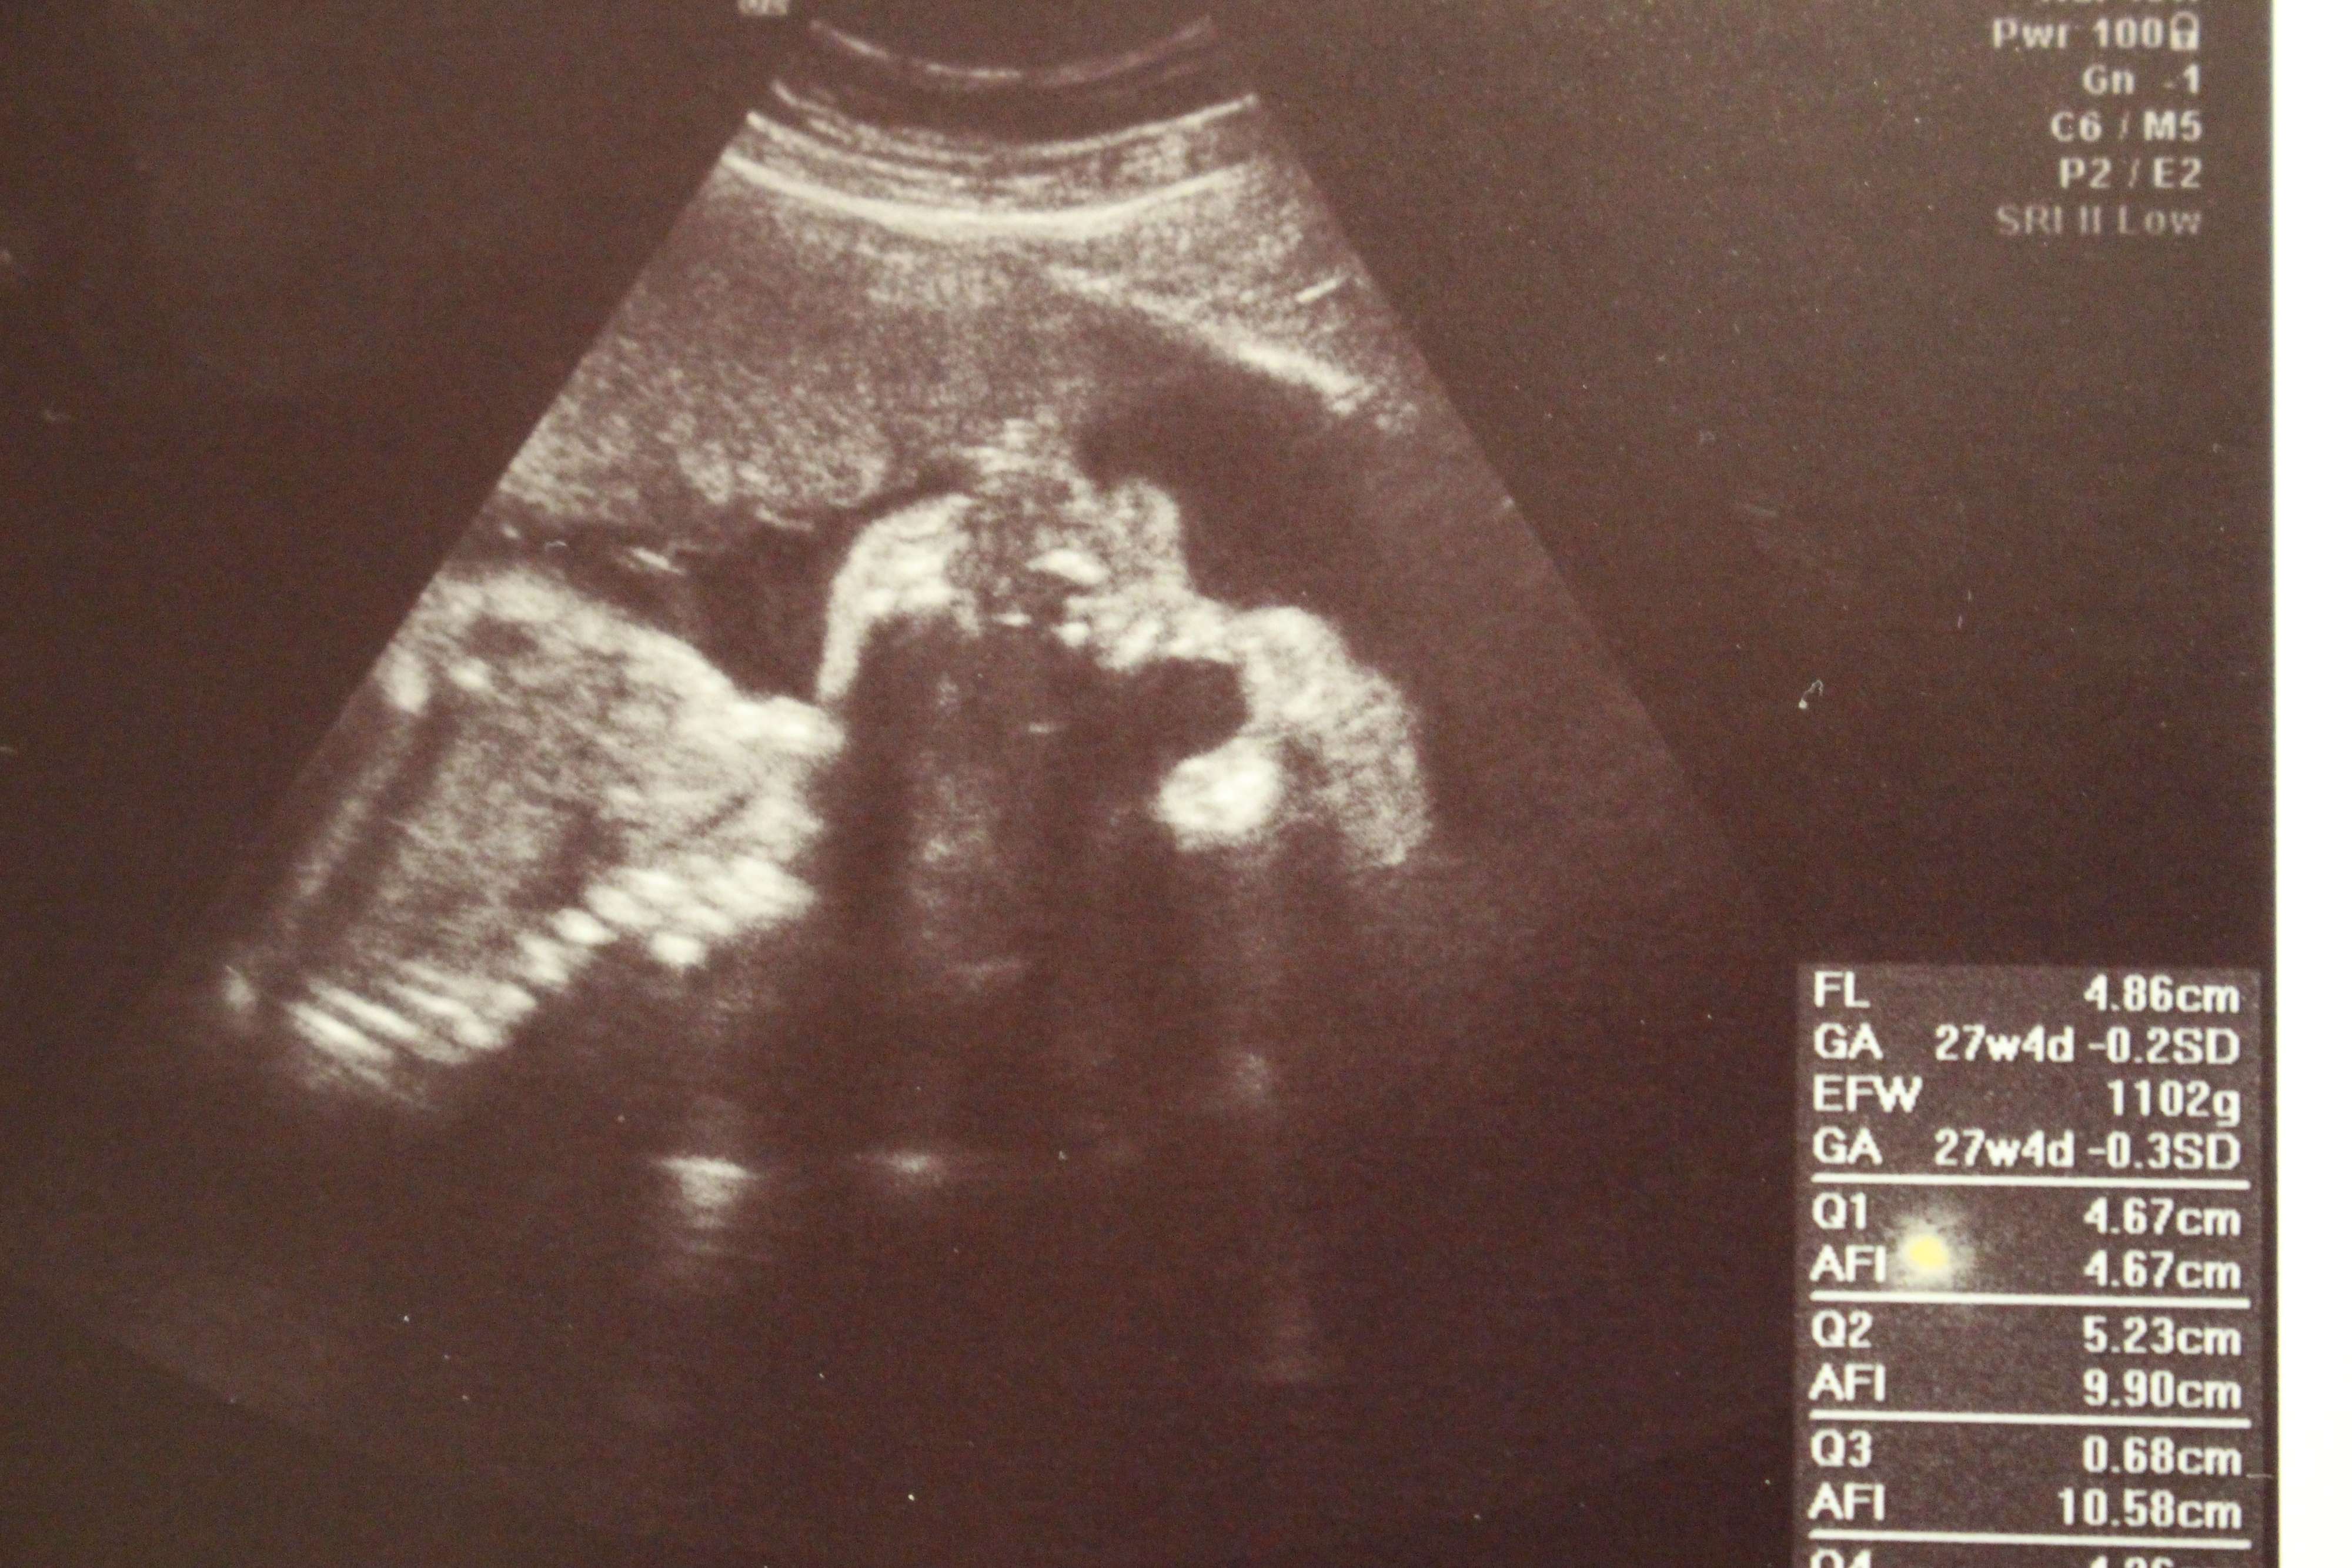

妊娠27週目のエコー写真

管理入院中は、ずっとベッドで安静第一に過ごさねばなりませんが、毎日看護師さんが赤ちゃんの心音を確認してくれるので安心でした。